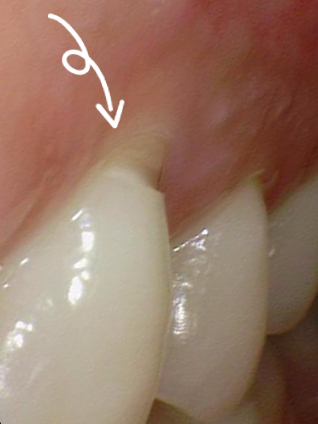

치경부마모증 사진

치경부 마모

치아 목 부위의 치아 겉부분이 패여 있는 것을 볼 수 있습니다. 이런 치경부 마모로 인해 시린증상이 흔합니다. 치아 속에는 치아마다 치아신경이 있는데 이 치아 중간에 있는 치아신경이 치아로 덮혀있어야 하는데 치아가 패이면서 바깥환경과 가까워지니 많이 시리게 됩니다.

환자분들이 "잇몸이 패였어요"하고 찾아오는 경우가 많으신데 잇몸이 패였다기 보다는 치아가 v자 모양으로 패인 것이라고 생각하면 되겠습니다. 이런경우에 잇몸패임 은 잘못된 표현이라고 볼 수 있겠습니다.